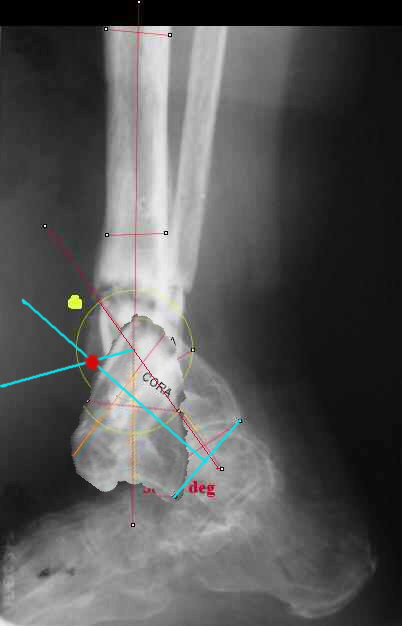

TDVC> I played with your image using some orthopedic software

TDVC> we have been developing for digital image analysis.

TDVC> a correction around the CORA through the old # will restore

TDVC> alignment without much translation.

Maybe my "embedded software" is obsolete but it hints me to place hinges at the yellow point - this must result with alignment and some lengthening without translation. What do you think?

Re the CORA.:

I think that if you locate the hinge at that site and then you rotate the foot about this point with out distraction you will be perfectly lined up. If you distract in the axis of the proximal tibia then rotate, it should still work (the hinge should still be located in the mid tibial axis). But, if you distract out of that axis then you will get translation. Does that make sense?

I looked at your image. I presume your yellow marker is the hinge axis? I think this should be at the CORA.